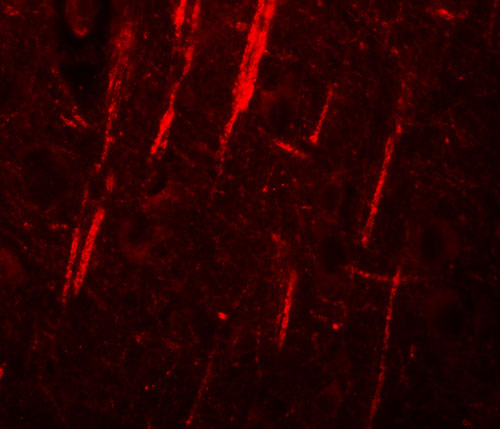

Immunofluorescence of NALP12 in human brain tissue with NALP12 antibody at 20 μg/mL. |